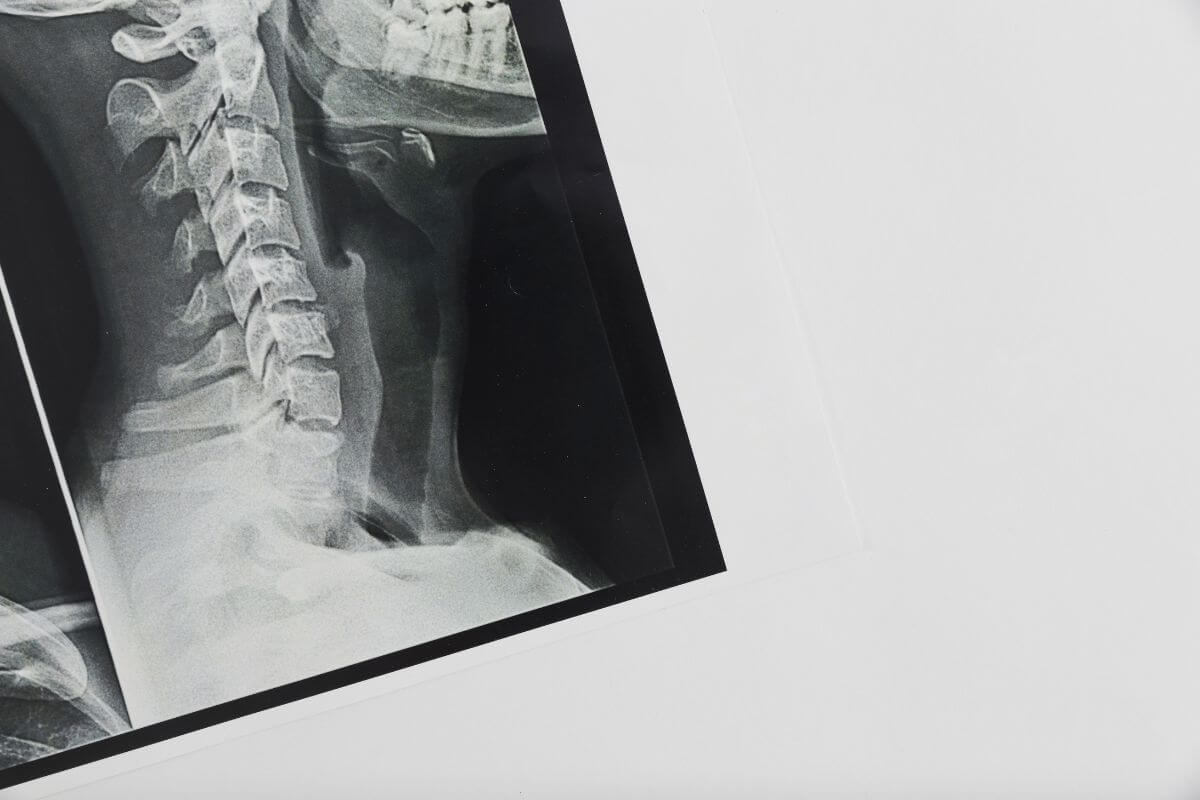

Képalkotó eljárások: röntgen és MRI

A képalkotó diagnosztika kulcsfontosságú a nyaki gerincsérv azonosításában. Az orvos ezeket az eszközöket használja az állapot súlyosságának felmérésére.

- Röntgen: Az első lépés gyakran egy röntgenfelvétel, amely megmutatja a csigolyák helyzetét és az esetleges meszesedéseket. Bár a röntgen nem mutatja ki a porckorongok állapotát, a csigolyák közötti szűkületek utalhatnak sérvre.

- MRI: A mágneses rezonancia képalkotás részletes képet ad a porckorongokról és az idegekről. Ez az eljárás a sérv méretét és pontos helyét is feltárja.

- CT-vizsgálat: Ritkább esetekben, ha az MRI nem lehetséges, a CT alternatívát nyújthat a gerinc állapotának elemzésére.

A képalkotó eljárások segítségével az orvos pontos kezelési tervet állíthat össze, amely személyre szabottan igazodik a beteg állapotához.